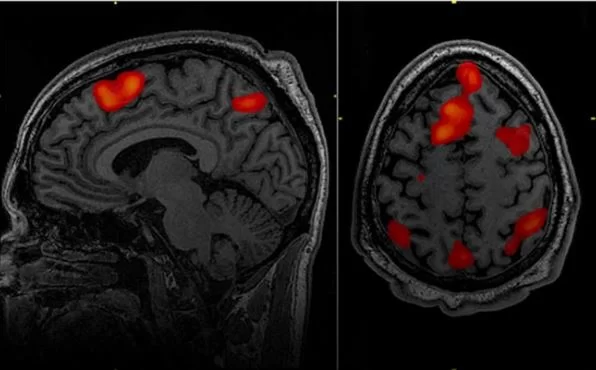

Περιλαμβάνει διάφορες τεχνικές όπως τη μαγνητική τομογραφία με ειδικές ακολουθίες (λειτουργική μαγνητική τομογραφία – fMRI), την ηλεκτρική διέγερση του εγκεφάλου, το διακρανιακό μαγνητικό συντονισμό κ.α.

Μερικοί όγκοι του εγκεφάλου αναπτύσσονται ή/και επεκτείνονται σε περιοχές του εγκεφάλου οι οποίες είναι κρίσιμες (eloquent), με την έννοια ότι ενδέχεται να περιέχουν σημαντικές λειτουργίες όπως για παράδειγμα η κίνηση και ο λόγος. Είναι σημαντικό ο χειρουργός να γνωρίζει πρίν το χειρουργείο αλλά και κατά τη διάρκεια της επέμβασης που ακριβώς βρίσκονται αυτές οι περιοχές σε σχέση με τον όγκο, προκειμένω να αποφύγει να προκαλέσει βλάβη.